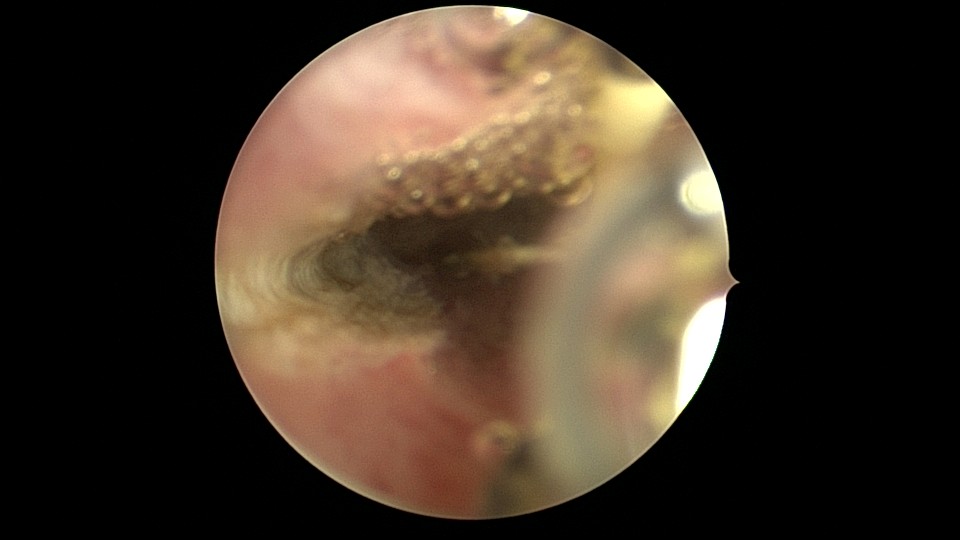

患者26岁,G7P1,剖宫产1次。2019年10月药流不全,行清宫术,术后闭经半年,后月经紊乱,周期28天~60天,月经量少。2021年4月,闭经50+天,B超提示宫腔粘连,宫腔镜见宫颈管上段封闭粘连,宫腔广泛粘连,AFS评12分(最高分)。宫腔镜电切分粘,恢复宫腔形态,显露双侧输卵管开口,宫腔防粘连复发处理,2021年5月宫腔镜二探取球囊。2021年7月自然妊娠,门诊人流并安环。2021年9月,月经推迟,B超提示宫腔粘连,节育环嵌顿,行宫腔镜取环并分粘,2021年10月二探取球囊。2021年12月放置皮埋避孕,2022年3月要求取出皮埋棒。2023年8月初自然妊娠,药流不全,2023年8月底行宫腔镜清除残留胚物。2024年2月自然妊娠10周,2024年4月初妊娠3+月(BPD2.6cm),坚决要求终止妊娠,行宫腔镜辅助终止妊娠。2025年6月因异常子宫出血再次宫腔镜分粘,2025年7月二探取球囊。现31岁,G10P1,前后共做了8次宫腔镜,术后多次自然妊娠,患者妊娠中途均选择了终止妊娠。